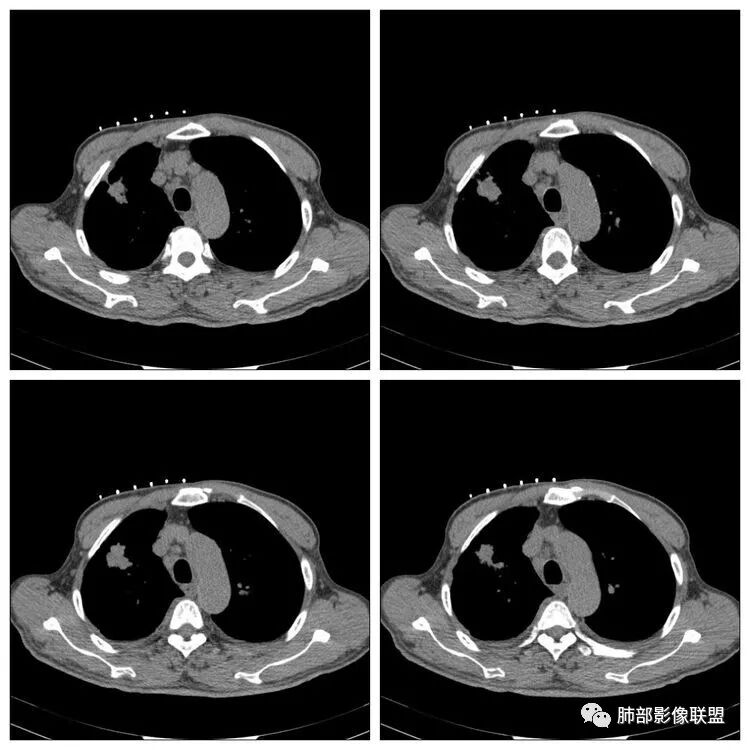

傅昌瑜:老年男性,有贲门癌史,右上团块影分叶毛刺胸膜凹陷→恶性可能,周围有卫星灶→良性可能。右侧胸廓塌陷,右侧胸膜有较多结节,双侧胸腔少量积液。整体考虑良性可能→结核可能性大。建议增强及穿刺检查。

THINKER:右上肺前段结节,胸膜凹陷征,整体收缩,有空泡征,胸膜多发结节,纵隔淋巴结肿大,双侧胸腔少量积水;考虑恶性,原发腺癌>转移;

老年男性,贲门癌病史。胸CT:右侧胸廓塌陷,右肺体积变小,右肺上叶大结节,深分叶、胸膜牵拉、毛刺,周围卫星灶,两肺多发微结节影,纵隔多发肿大淋巴结,先考虑恶性,结核待排。

老年男性,有贲门癌病史,右肺上叶结节,有分叶毛刺征,胸膜牵拉,周围多发微小结节,纵隔淋巴结肿大,双侧少量胸水,考虑恶性结节可能,结核不排,建议增强。

红日东升:老年男性,贲门癌病史。右肺尖段病灶,收缩明显,多发毛刺,胸膜牵拉,局部胸膜增厚牵拉,周围卫星灶,右上叶体积较小。考虑炎性肉芽肿,结核可能,鉴别腺癌。

蔡磊:右肺上叶结节,边缘较清,边缘有收缩,临近胸膜局限性增厚,周围见散在卫星灶,支气管未见明确截断,病灶内密度基本均匀,纵隔内多发增大淋巴结,总体考虑结核,建议增强后再观察,虽然有胃癌病史,转移瘤不是太像。

南边:纵隔淋巴结有融合的迹象,边界不清,右侧内乳动脉增粗了很多;怀疑纵隔淋巴结用血很大。有结核的话并不代表不能得癌肿;一般情况下结核附近的病灶呈条索树芽状;综上所述恶性不能完全排除。

这种纵隔右移提示病程较长,腔静脉后见轻度增大淋巴结。